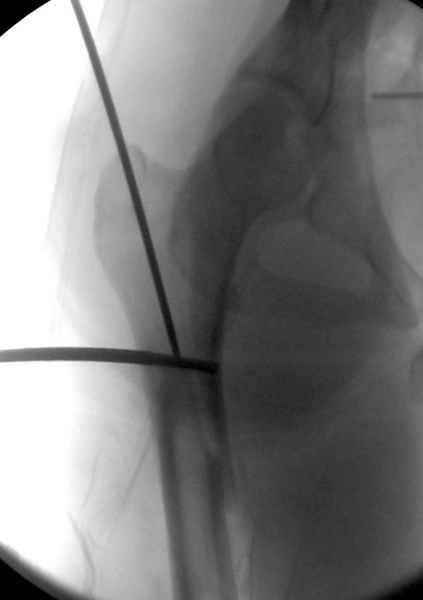

Как раз недавно у меня был примерный случай: больному 36 лет, поступил ночью, травма в результате мотоциклетной аварии, кроме чрезвертельного и спирального перелома левого бедра имеется переломы костей предплечья с этой же стороны. Скелетное вытяжение, а на следующий день больной про оперирован на ортопедическом столе с дистракцией. Чтобы не расколоть чрезвертельный перелом провели временную спицу ближе к переднему кортексу, из малого разреза костодержатель для репозиции, а фиксацию провели антиградным штифтом. Этапы операции на снимках.

Второй случай тоже репозиция из малого доступа, больному 19 лет, множественные огнестрельные повреждениия конечностей, живота и черепа, правая конечность холодная, без пульсации. Ортопедический диагноз: огнестрельный перелом правого бедра. При срочной ангиографии повреждения сосудов не подтвердилось, конечность из-за ургентности состояния больного зафиксирована временным наружным фиксатором и больной оставлен на операционном столе для срочной лапаротомии хирургической службой.

Больной долго оставался нестабильным, только на 14 день удалось заменить на антеградный интромедуллярный штифт TFN (trochanteric femoral nail) SmithNephew. После неудачной попытки закрытой репозиции, несмотря на использование "joystick", проксимальный стержень от

наружного фиксатора, (перелом начал срастаться) репозицию провели из малого доступа, затем остальные этапы операции.